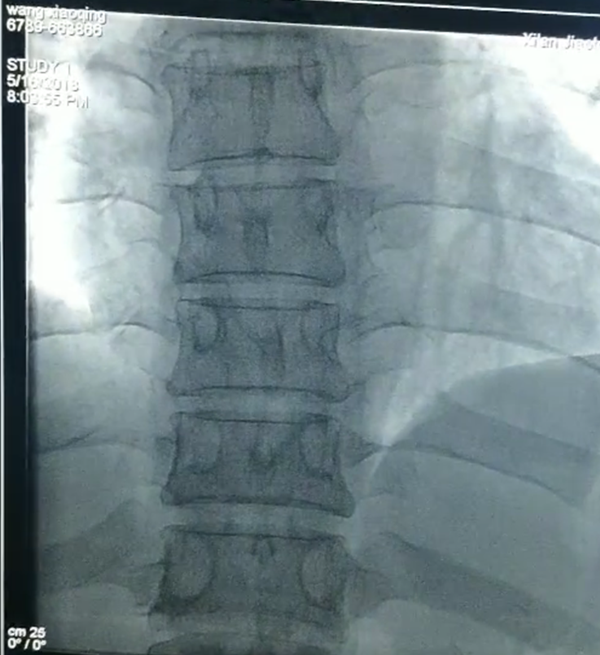

断裂入体内的导管

消毒铺巾以最快速度完成,穿刺,确认部位,放入网篮导丝,寻找断裂残端,小心翼翼拉出断裂的导管,一整套手法,董新教授前后用了仅十余分钟!断裂体内的导管直径约1.5mm,长约41mm,管子抓出来那一刻全体欢呼雀跃,掌声一片。